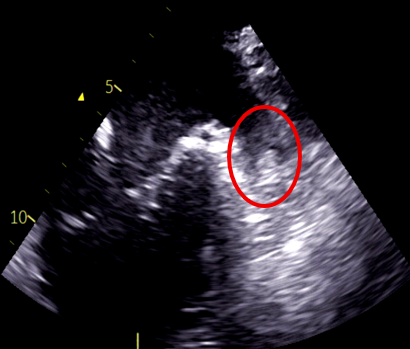

Electrocardiogram showed atrial fibrillation with a heart rate of 116 bpm and no significant ST-segment changes. Chest radiography showed cardiomegaly. Laboratory analysis showed an elevated NT-proBNP of 6103pg/mL. Transthoracic echocardiography demonstrated an ejection fraction of 15%, left atrial diameter of 60mm, global wall motion abnormalities. Transesophageal echocardiography confirmed the presence of a thrombus in the LAA.

The patient had reduced left ventricular function, and tachycardia-induced cardiomyopathy was initially suspected. We therefore aimed for early restoration of sinus rhythm. Despite treatment with rivaroxaban, the patient developed a cardioembolic stroke, and a thrombus persisted in the LAA. Anticoagulation was switched to warfarin. During stroke rehabilitation and optimization of cardioprotective therapy, we monitored the thrombus for resolution, but it remained unchanged. Because an LAA occlusion device cannot be used in the presence of an existing thrombus, and thoracoscopic LAA resection is feasible when the thrombus does not extend to the LAA base, we decided to perform thoracoscopic LAA resection on hospital day 70. Intraoperative transesophageal echocardiography confirmed the absence of thrombus at the LAA base before resection. A thrombus was found within resected LAA specimen. However, postoperative computed tomography on hospital day 79 revealed hypoattenuated thickening (HAT) at the resection stump, suggestive of thrombus formation. Transesophageal echocardiography confirmed this finding. After intensifying warfarin management, the thrombus resolved approximately 20 days later. Catheter ablation was subsequently performed on hospital day 115, and the patient has since maintained sinus rhythm.